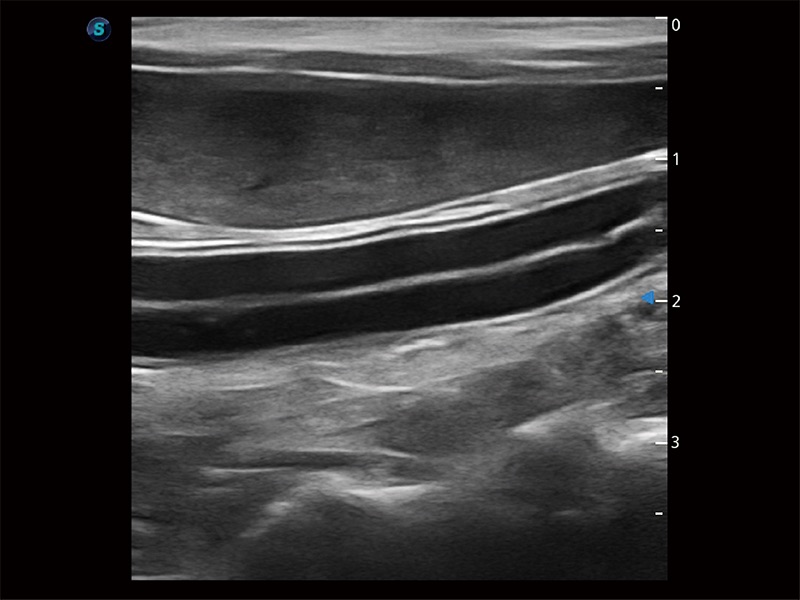

高性能和先进的临床应用工具可以为动物医生提供临床信心。ProPet 80 搭载了先进的腹部和浅表应用工具,帮助医生在日常临床实践中发挥前所未有的作用。

极大提升超低速微细血流的检出能力,同时更精准地滤除软组织和超声信号,为兽用医生提供以往无法通过常规血流获得的疾病诊断信息。

在传统二维血流成像的基础上,呈现血流的立体感,具有动感的生命力之美。即便是微小的血管也能轻松应对,提高了血流的视觉敏感性。